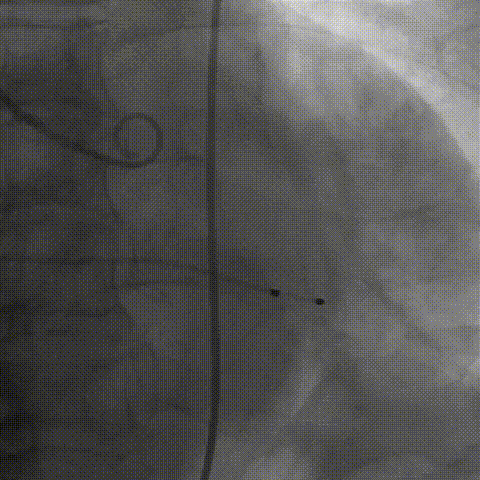

2026年伊始,TaurusTrio经导管主动脉瓣系统在复旦大学附属中山医院,浙江大学医学院附属第二医院,中国医学科学院阜外医院,首都医科大学附属北京安贞医院,四川大学华西医院等多家临床中心成功开展上市后全国首批植入。这不仅是TaurusTrio正式走向广泛临床应用的重要里程碑,更标志着中国单纯主动脉瓣反流介入治疗正式迈入了“心键合璧”的全新纪元。